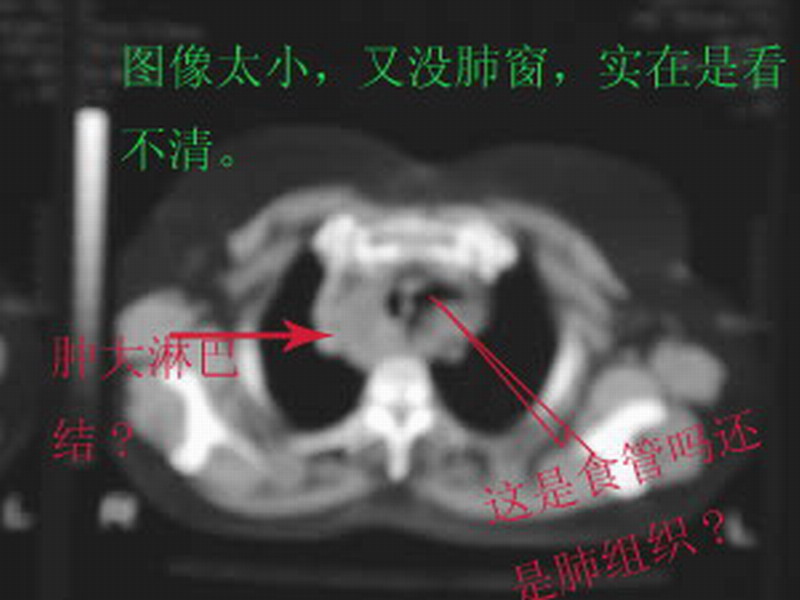

感谢suncl战友调的图像,好看多了。不过,您的诊断我不是很支持。

气管右旁的病灶我考虑是胸内甲状腺肿,它与颈部甲状腺一脉相连。左旁的病灶因为没有肺窗,首先考虑左肺尖部胸膜粘连并包裹的部分肺组织,食管问题的可能性应该比较小。